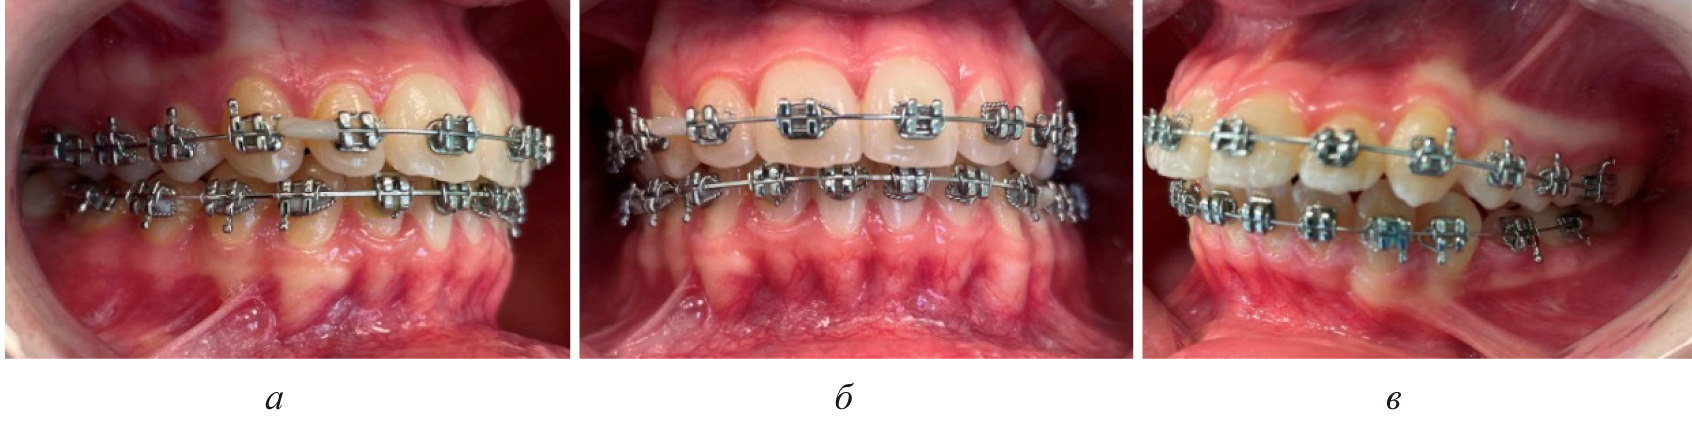

Смещение вторых постоянных моляров, как правило, было в меньшей степени выражено, чем отклонение от нормы других показателей биометрической диагностики. Достоверных различий при оценке положения вторых моляров на стороне ретенции и противоположной ей нами не отмечено (р ˃ 0,05). Смещение центральной точки дуги и изменения диагональных размеров резцово-клыковой и резцово-молярной диагонали способствовало смещению линии эстетического центра и нарушению смыкания пар зубов-антагонистов, которое было более выражено на стороне ретинированного зуба (рис. 3).

Последующие этапы ортодонтического лечения техникой эджуайс проводились с учетом общепринятого протокола и этапности смены металлических дуг, что способствовало нормализации окклюзионных взаимоотношений (рис. 5).

Рис. 3. Окклюзионные взаимоотношения справа (а), спереди (б) и слева (в) у пациента с односторонней ретенцией второго премоляра

Рис. 5. Окклюзионные взаимоотношения справа (а), спереди (б) и слева (в) на завершающем этапе лечения